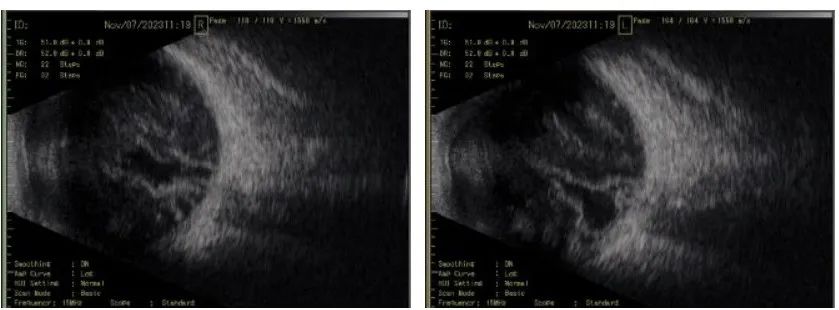

圖 | 患者劉先生術(shù)前玻璃體混濁情況

? ? ? 原來,劉先生患有一種罕見的眼病——玻璃體淀粉樣變性。3年多前,劉先生開始感覺到雙眼視物不清,且癥狀不斷加重。在國內(nèi)多個(gè)知名大醫(yī)院來回診治數(shù)次均無明顯效果,同時(shí)視力變得越來越差,只能看到眼前模糊的影子。在他感覺希望越來越渺茫的時(shí)候,他慕名來到了眼視光醫(yī)院,幸運(yùn)地找到了眼底外科柯治生主任醫(yī)師。

? ? ? 柯治生主任深入分析劉先生的病情后,診斷為“淀粉樣變性”。鑒于患者年輕,雙眼患病,生活工作不能自理,唯有手術(shù)治療才可能有一線機(jī)會(huì)。在和患者及家屬深入溝通之后,劉先生表示堅(jiān)決要求手術(shù)。